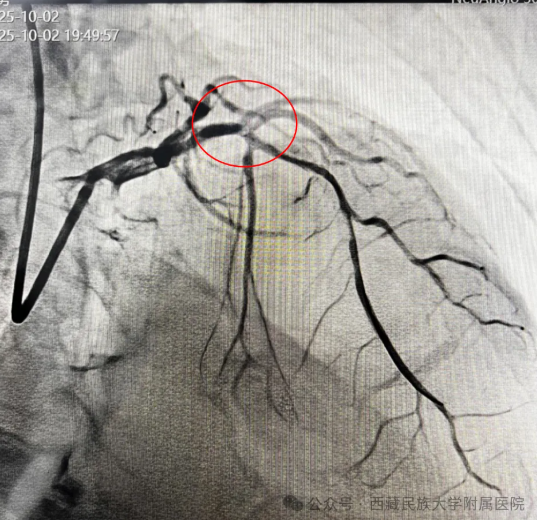

(图4:冠脉介入结果,前降支血流恢复)

手术在紧张而有序的氛围中展开。孙丽荣医师带领团队沉着冷静、操作娴熟,在数字减影血管造影(DSA)精准引导下,顺利将导管送至病变部位。随着闭塞血管被成功开通,心肌血流恢复灌注,患者上腹痛症状迅速缓解,生命体征逐步平稳。术后,当患者露出安心的笑容时,连续奋战的医护人员才稍稍松了一口气。这一刻,是医者仁心的最好见证,连日坚守岗位的医护人员也由衷感到欣慰。